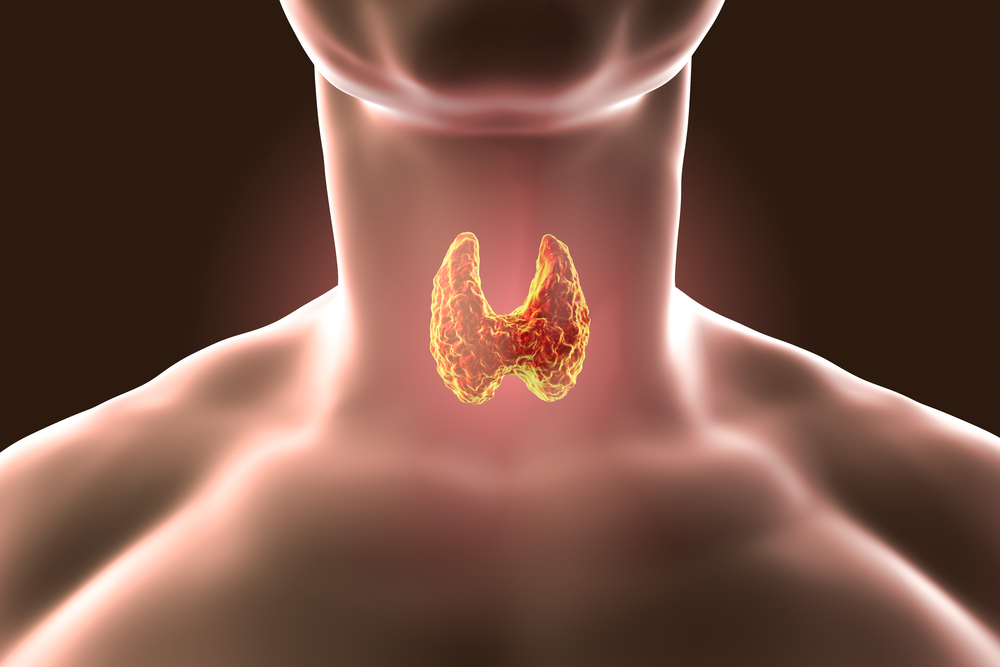

Wendy took a break from hosting her TV show after she started to suffer complications from her thyroid issues and Graves’ disease. Denise Pate, MD — an internal medicine physician with Medical Offices of Manhattan Opens a New Window. — previously offered some insight about the auto-immune disorder and how it might affect Wendy’s health.

“Graves’ disease is an auto-immune disorder that causes overproduction of thyroid hormone leading to hyperthyroidism. It is caused by an antibody called thyrotropin receptor antibody (TRAb) binding to thyroid cell receptors resulting in the increased release of thyroid hormones and thyroid growth that can alter our body’s function,” Dr. Pate — who does not treat Wendy — explained to Life & Style. “Some of the common symptoms associated with Graves’ disease are palpitations, tachycardia, hand tremors, weight loss, muscle weakness, fatigue, erectile dysfunction [for men], and irregular menstrual cycles [for women].”